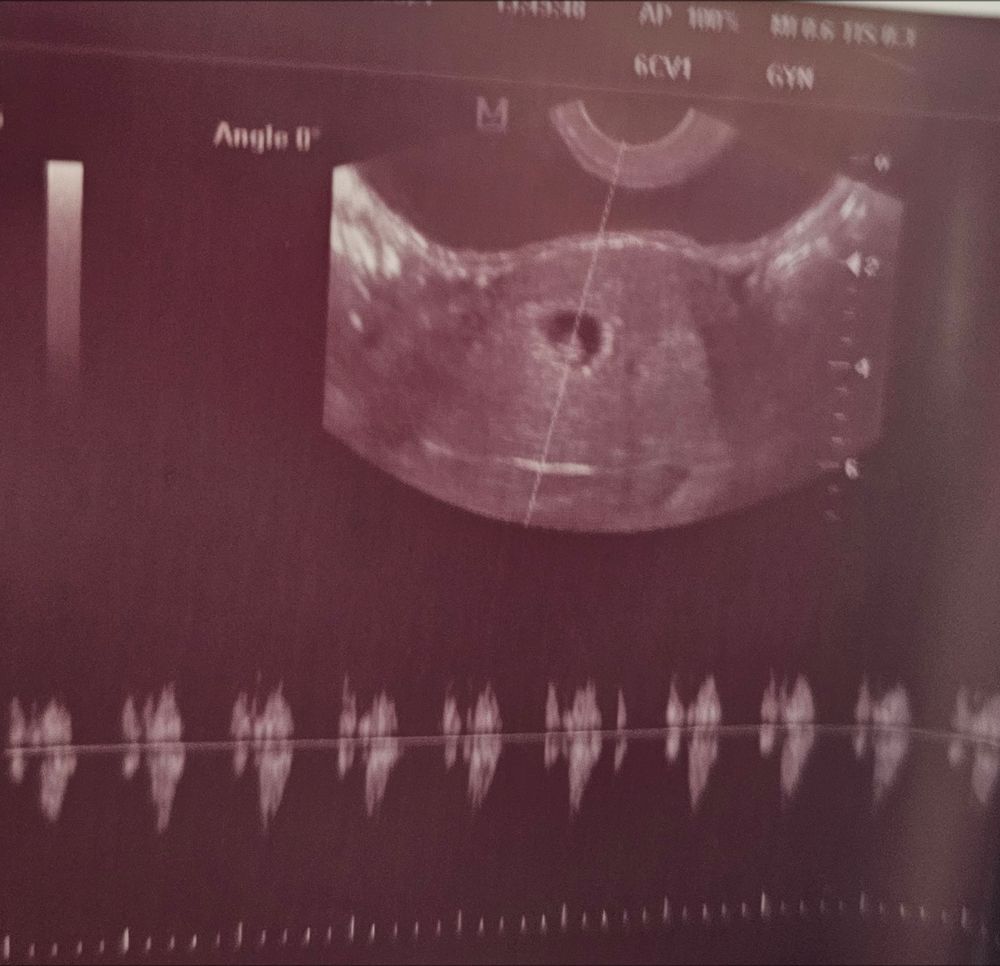

27 дпп первое узи и первое в моей жизни сб💞

35дпп мы счастливы❤️😍 Узи 7.1 недель